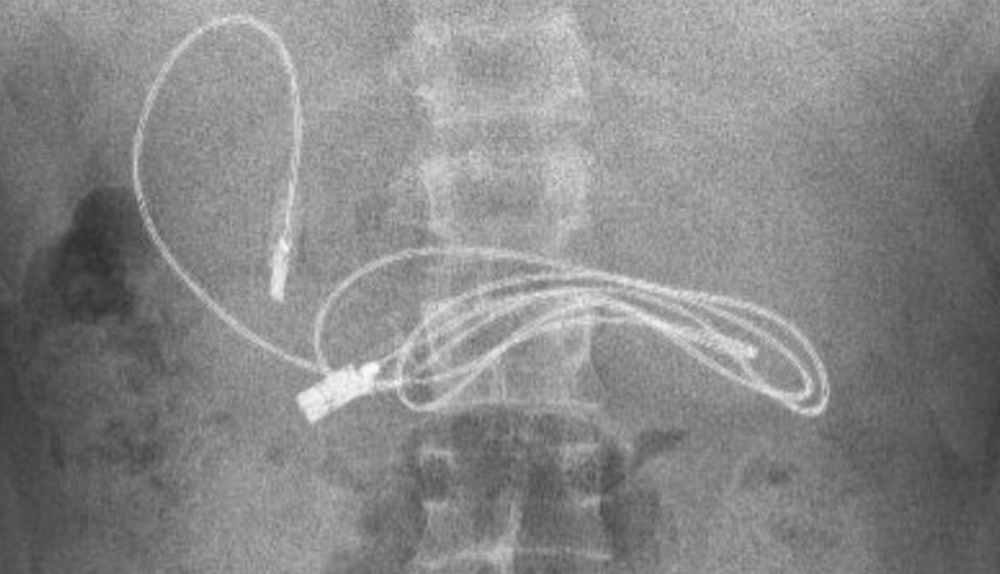

Se quedaron con la boca abierta cuando en la radiografía se podía divisar claramente estos dos objetos. De inmediato, el joven fue trasladado a un especialista, concretamente al hospital de Firat en Elazig, donde el jefe del departamento de gastroenterología, hepatología y nutrición pediátrica no podía creer que el menor tuviera en su interior semejantes objetos.

Ante esta situación, fue intervenido con el fin de extraer el cable y la goma lo antes posible. Los médicos han compartido en sus redes sociales la sorprendente radiografía y explicaron que el médico realizó una endoscopia a través de su boca para llegar al punto donde se encontraba el cable. Según recoge Telecinco, fue una tarea complicada porque uno de los extremos había pasado al intestino delgado.